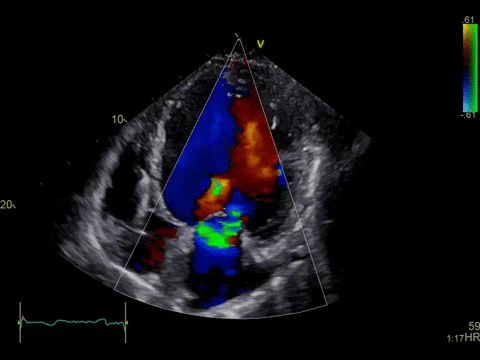

Farbdoppler-Ultraschall wird verwendet, um den Blutfluss anzuzeigen. Es verwendet verschiedene Farben und Helligkeit, um die Richtung und Geschwindigkeit des Blutflusses anzuzeigen, was uns hilft, Blutgefäße und das Herz zu beobachten.